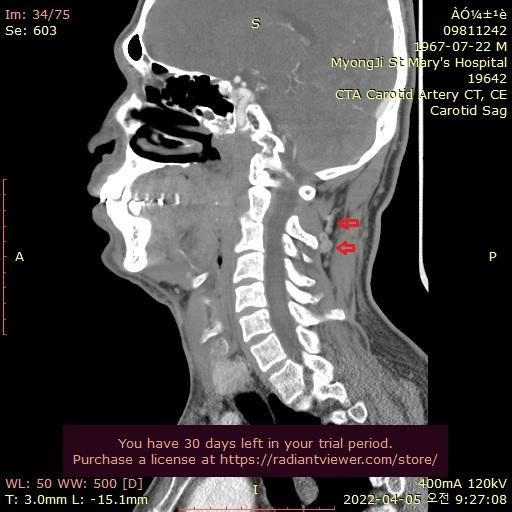

그런데 가까운 의원에서 그때의 영상을 보다가 그림과 같이 목 뒤쪽에 정맥혈관에 기형이 심한것을 알았습니다.

울퉁불퉁 하고 아주 굵어져서 혈액 순환이 안도는것으로 보입니다.

자료 찾아보니 심부경정맥 인것 같습니다. 내경정맥등과 함께 뇌의 혈액을 심장으로 빼내서 보내주는 중요한 혈관으로 보입니다.

기형이 심해서 혈액이 잘 안 빠지는 것일까요?

• 2번 째 사진